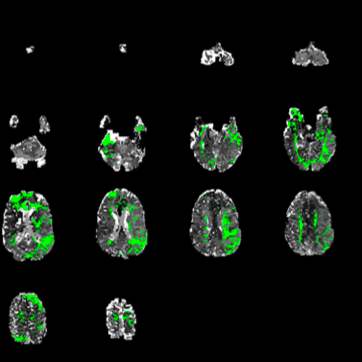

Computed Tomography-Based Imaging Algorithms for Patient Selection in Acute Ischemic Stroke

Pulli B, Heit JJ, and Wintermark M (2021) Neuroimaging Clin N Amer May;31(2):235-250. doi: 10.1016/j.nic.2020.12.002.Epub 2021 Mar 23.

Non-contrast dual-energy CT virtual ischemia maps accurately estimate ischemic core size in large-vessel occlusive stroke

Wolman DN, et al. (2021) Scientific Reports Mar 24;11(1):6745. doi: 10.1038/s41598-021-85143-3.

Perfusion imaging-based tissue-level collaterals predict ischemic lesion net water uptake in patients with acute ischemic stroke and large vessel occlusion

Faizy T, et al. (2021) JCBFM Feb 8;271678X21992200. doi: 10.1177/0271678X21992200.

CT perfusion core and ASPECT score prediction of outcomes in DEFUSE 3

Kim-Tenser M, et al. (2020) Int J Stroke Mar 31;1747493020915141. doi: 10.1177/1747493020915141.